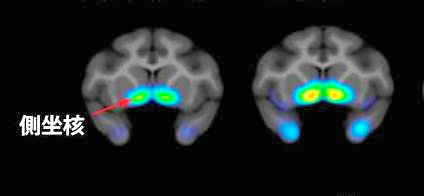

麻酔薬に使用のケタミン、抗うつ剤に有効-理研、動物で実証

理化学研究所ライフサイエンス技術基盤研究センターの尾上浩隆チームリーダーと山中創特別研究員らのグループは、麻酔薬として使われているケタミンが、新しい抗うつ剤として有効となる可能性があることをサルでの実験で明らかにした。ケタミンを投与したサルの脳を陽電子 ...日刊工業新聞 ·